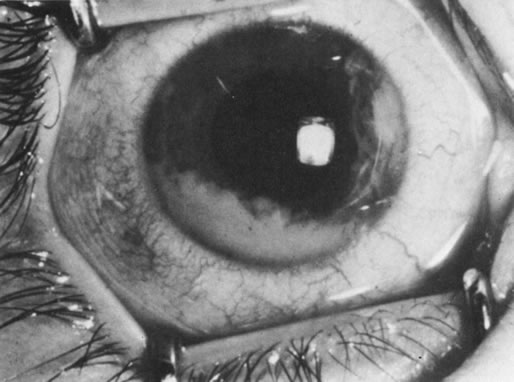

Unfortunately, imaging studies are not always diagnostic. The A- and B-scans shown in Figures 3 and 4 were from a patient with unilateral media opacity referred for evaluation and treatment of a presumed uveal melanoma. Occasionally, if the cataractous lens is scanned tangentially, artifact can occur. A repeat ultrasound at our institution was negative for tumor, and the referral ophthalmologist who performed a cataract extraction noted that no tumor was present and that the patient has an excellent visual outcome. In contrast, the patient shown in Figure 5 was referred with a presumed uveal melanoma with secondary inflammation and a history similar to that described for the patient shown in Figure 111 Ultrasound and CT examinations were not diagnostic. Because the eye was blind and painful, it was enucleated, and an extremely necrotic uveal melanoma was noted histologically. In some necrotic melanomas, the fundus cannot be visualized and the diagnosis cannot be established with imaging studies. Very rarely, a necrotic uveal melanoma can produce sufficient pigment dispersion into the vitreous to obscure the correct diagnosis.12

In addition to producing media opacity, inflammation, and cataract, uveal melanomas can also produce other signs that may lead to the incorrect diagnosis of uveitis. Anterior melanomas, especially those that involve the ciliary body, often produce dilated episcleral vessels (sentinel vessels) that occasionally have been misdiagnosed as scleritis (Fig. 6).